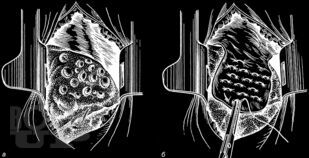

В руководстве представлены современные данные о механизмах развития наиболее частых неотложных заболеваний органов грудной и брюшной полостей, возникающие при них патологические изменения. Подробно изложены методы исследования, диагностики, общие принципы интенсивной терапии, основы предоперационной подготовки пациентов, показания к оперативным вмешательствам, техника их выполнения, принципы послеоперационного ведения больных. Третье издание руководства (второе вышло в 2006 г.) дополнено главами, посвященными неотложным состояниям и хирургической тактике при остро возникших гинекологических заболеваниях, а также получающему развитие методу видеоторакоскопии в неотложной торакальной хирургии.